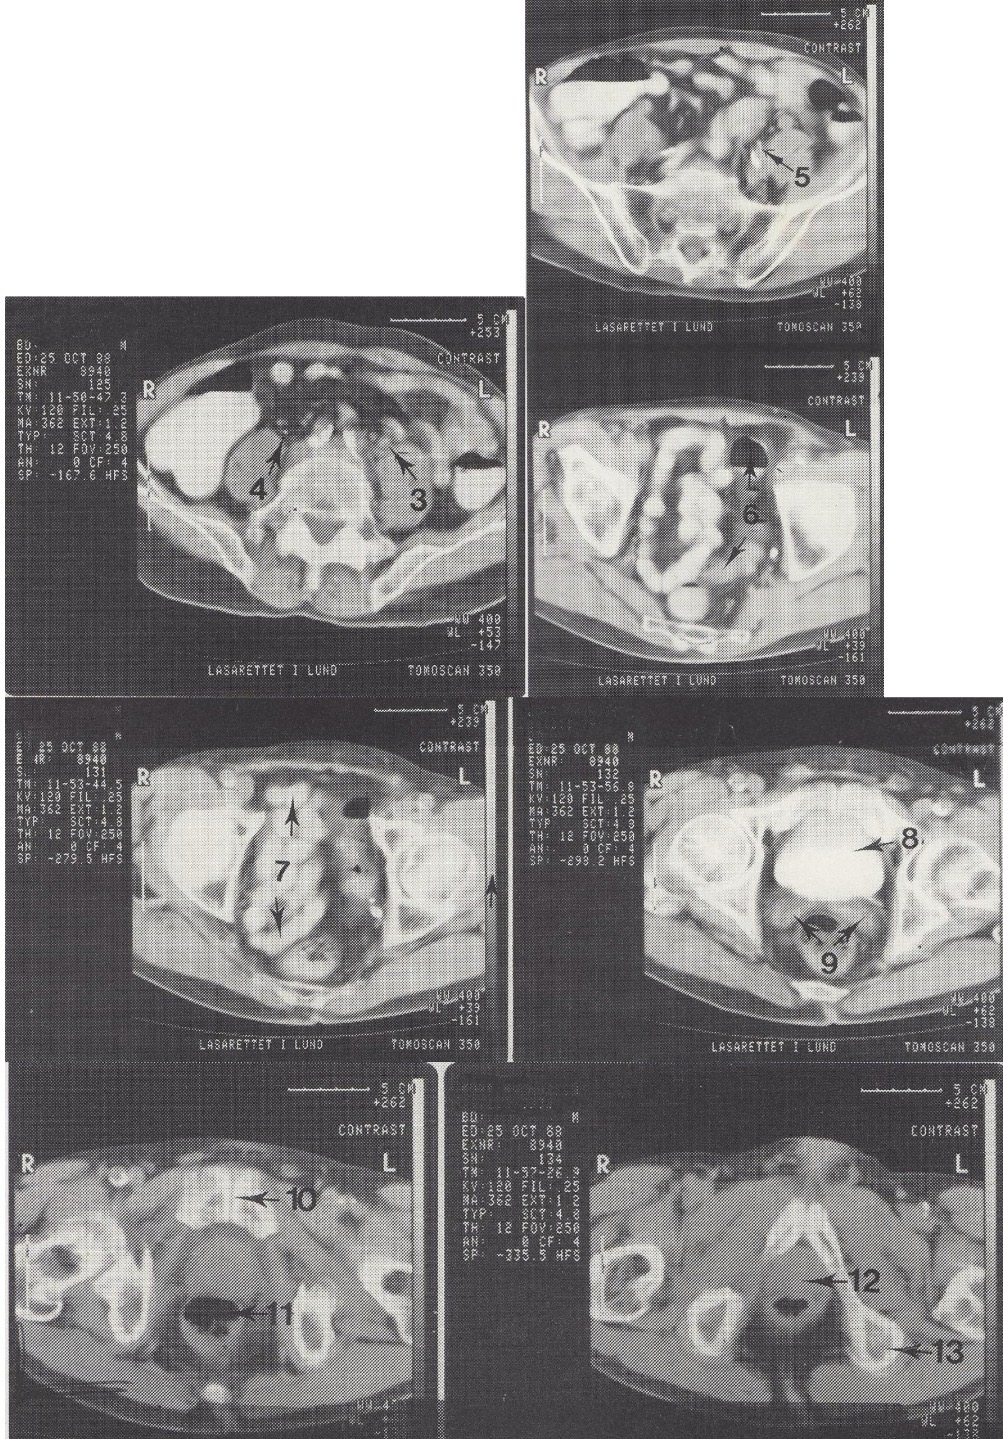

10

Symphysis pubica (gaktinė sąvarža)

11

Rectum (tiesioji žarna)

12

Prostata (priešinė liauka)

13

Tuber ossis ischii sin. (kairysis sėdimasis gumburas)

Metodika

KT pjūviai nuo juosmens slankstelių iki gaktinės sąvaržos apačios. Suleistas intraveninis kontrastas (išryškina šlapimo takus) ir išgertas kontrastas (išryškina žarnyną).

Radiniai

Gausūs apkalkėjimai (kalcifikatai) aplink pilvinę aortą ir vidines klubo arterijas. Kairysis šlapimtakis matomas priešais m. psoas major, jis šiek tiek išsiplėtęs.